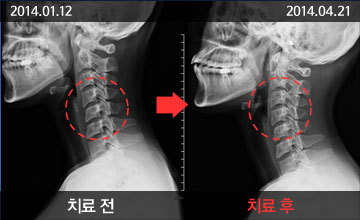

치료 전후 사례

- 턱관절 운동의 중심축이 되는 척추를 교정하여 일자목 형태의

경추가 정상으로 회복돼 턱관절의 구조적인 문제가 바로 잡아 짐

- 턱관절 운동의 중심축이 되는 척추를 교정하여 일자목 형태의